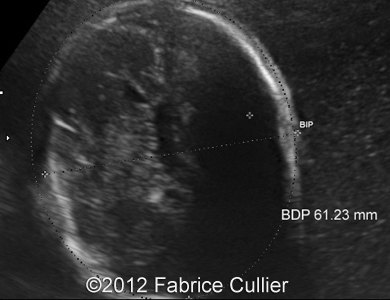

Images 1, 2: A transversal plane of the skull, too round (Brachycephaly).

1A

1B